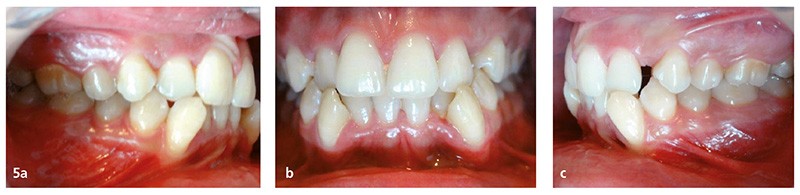

À la téléradiographie de profil (fig. 7), la patiente s’avère normodivergente (FMA à 27°). Une dissymétrie mandibulaire, acceptable, est à noter. Elle présente une normomaxillie (SNA = 81°) et une rétromandibulie (SNB = 77°). L’inclinaison incisive est normale au maxillaire comme à la mandibule (I/F = 110° IMPA = 91°).